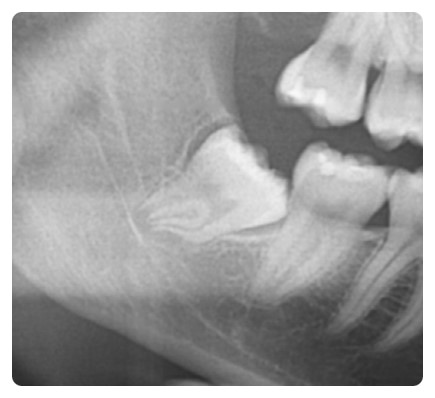

사랑니와 신경관이 붙어 있어 상당히 어려운 케이스입니다.

사진에서 보시는 것처럼 신경관과 사랑니 뿌리가

아주 가까이 붙어 있는 경우에는 상당히 조심을 해야 합니다.

잘못 해서 신경관을 건들기라도 한다면

안면 근육 마비 증세가 오고 한동안 상당히 고생을 할 수 있습니다.

사랑니 뽑기 전 엑스레이 사진입니다.